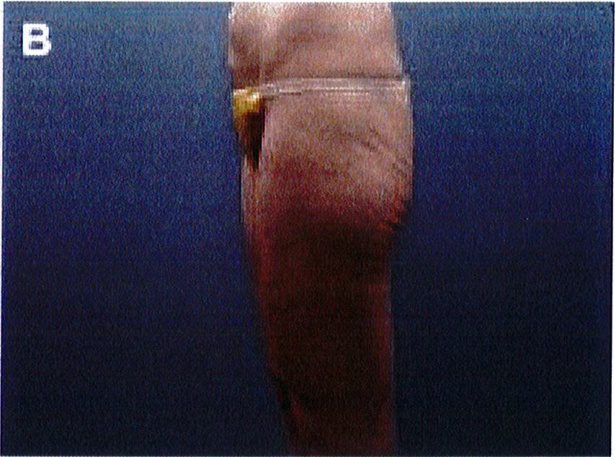

Hình. 11. (A, B) Bệnh nhân nữ 59 tuổi với vùng da mông chùng và xệ. (C,D) Hai năm sau phẫu thuật tạo hình thành bụng và tạo hình mông bằng phương pháp purse-string.Bênh nhân này bị tách vết mổ, sau đó đã đươc điều tri liền seo

Hình. 12. (A, B) Bệnh nhân nữ 37 tuổi với vùng mông dẹt và xệ. (C,D) Tám tháng sau phẫu thuật tạo hình thành bụng và tạo hình mông bằng phương pháp purse- string .

Hình. 13. (A, B) Một bệnh nhân 62 tuổi với vùng mông xệ và hình chiếu không thẩm mỹ. (C,D) Sau phẫu thuật 16 tháng tạo hình mông bằng phương pháp purse-string (đã tao hình thành bung trước đó).